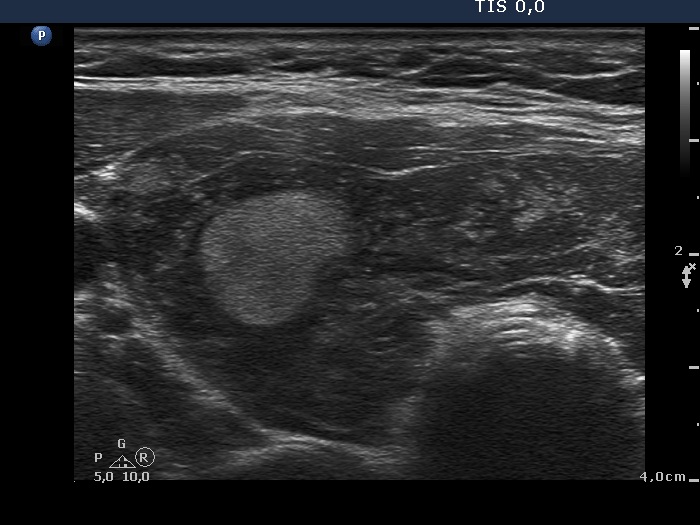

The thyroid gland is located in the neck, just above where your collarbones meet in the middle. Web chronic thyroiditis is caused by a reaction of the immune system against the thyroid gland. The disorder is also called hashimoto disease.

These antibodies cause inflammation in your thyroid gland. This disorder can be either painful or not felt at all. The thyroid gland is located in the neck, just above where your collarbones meet in the middle.

Web chronic thyroiditis is caused by a reaction of the immune system against the thyroid gland. The number of people who have hashimoto’s disease in the united states is unknown. There are four main types of thyroiditis:

Web hashimoto’s thyroiditis, also known as hashimoto’s disease, damages your thyroid function. Web hashimoto’s thyroiditis is also known as chronic lymphocytic thyroiditis or autoimmune thyroiditis. However, the disease is the most common cause of hypothyroidism, which affects about.

This means you develop antibodies [thyroid peroxidase (tpo) and/or thyroglobulin (tg) antibodies] that damage your thyroid gland. The disorder is also called hashimoto disease. The thyroid gland is located in the neck, just above where your collarbones meet in the middle.

This can last for a few weeks or months. Subacute thyroiditis is believed to be triggered by a viral infection. It often results in reduced thyroid function ( hypothyroidism ).